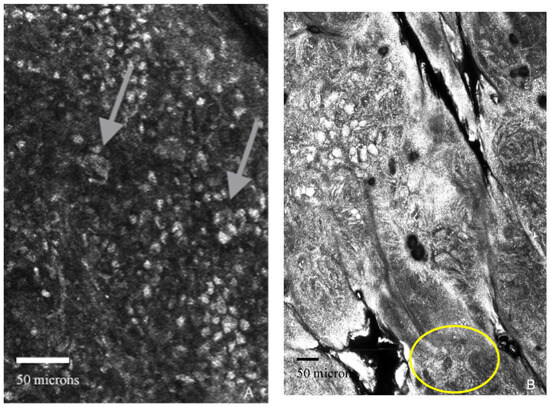

The patient preferred a non-invasive technique rather than a biopsy at first, so we decided to perform in vivo RCM examination (with the Vivascope 1500/3000 confocal microscope-Vivascope GmbH, Munich, Germany), which revealed pagetoid cells spreading in the upper epidermis, cell atypia, non-edged papillae, dermal inflammation, and nucleated cells in the dermis (Figure 3A), suggesting the diagnosis of melanoma.

Figure 3.

(A–D). Reflectance confocal microscopy aspects (VivaScope 1500/3000). (A) Arrows: pagetoid cells at the level of the epidermis; (B) yellow circle: small hyper reflective inflammatory cells; (C) yellow square: cerebriform nest; (D) yellow circle: disarray of dermal papillae.